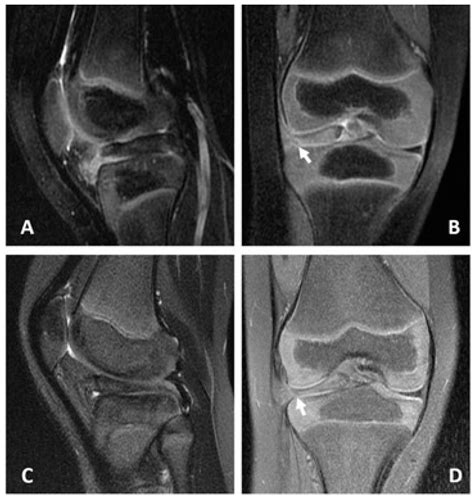

A bucket handle injury is a specific type of meniscal tear where the torn piece of the meniscus flips into the joint space, resembling the handle of a bucket. This type of tear is often more severe and can cause the knee to lock or give way. The meniscus is a C-shaped piece of cartilage that cushions the knee joint and helps distribute weight evenly. When it tears, it can lead to a range of symptoms that affect mobility and quality of life.

• Imaging Tests: X-rays, MRI, or CT scans may be ordered to visualize the meniscus and confirm the diagnosis. MRI is particularly useful for detecting meniscal tears and assessing the extent of the damage.